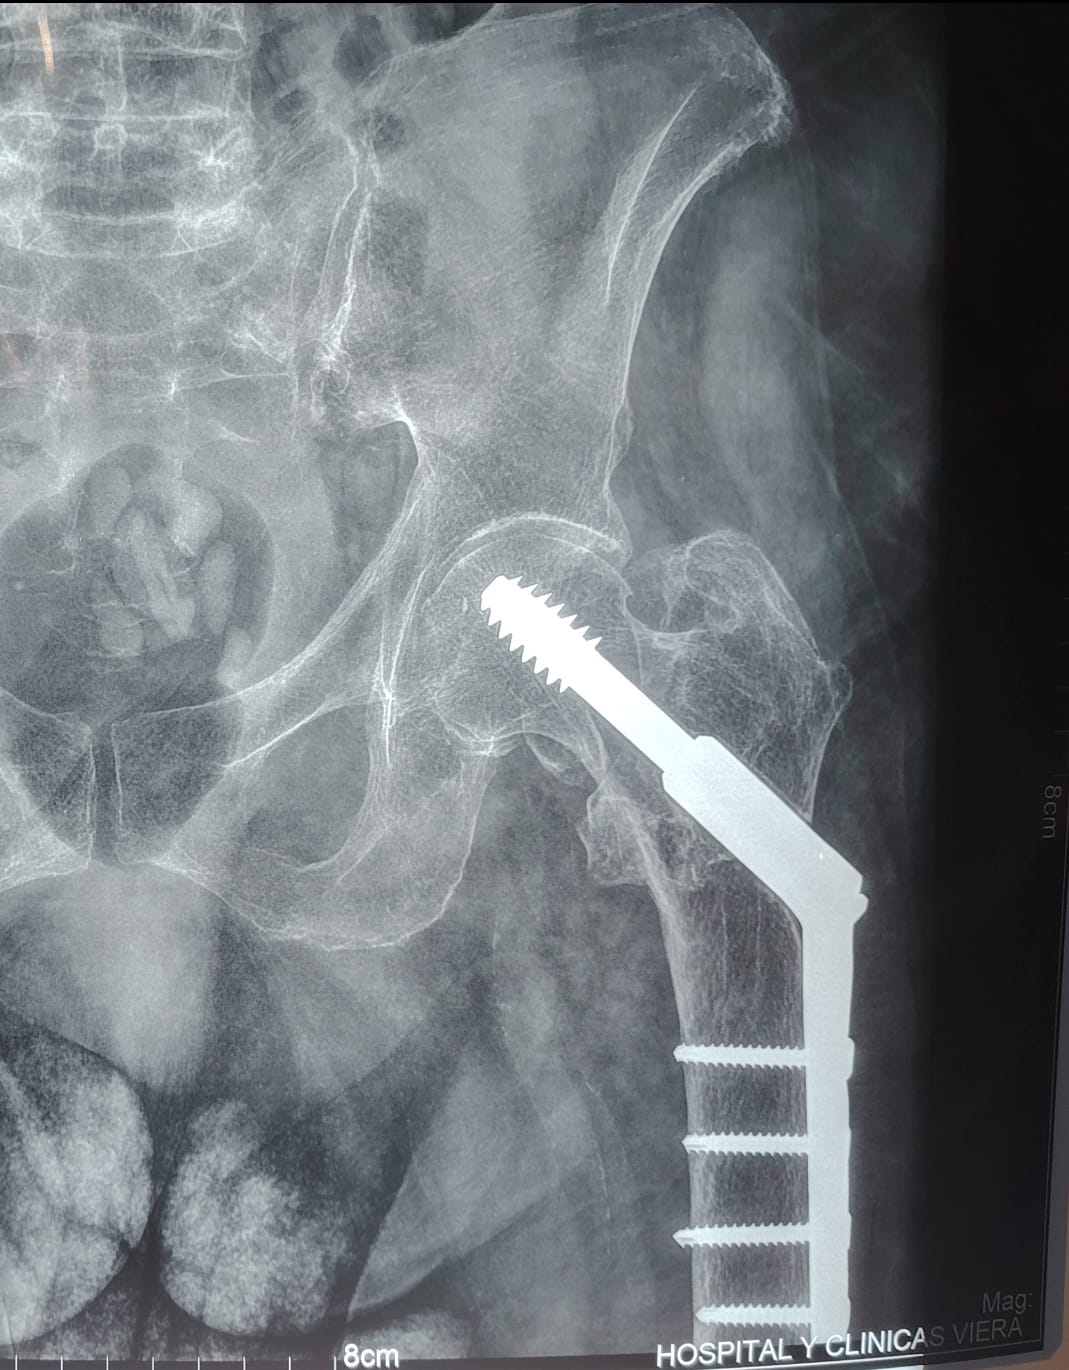

Imagen de fractura de cadera manejada con Tornillo Deslizante de Cadera